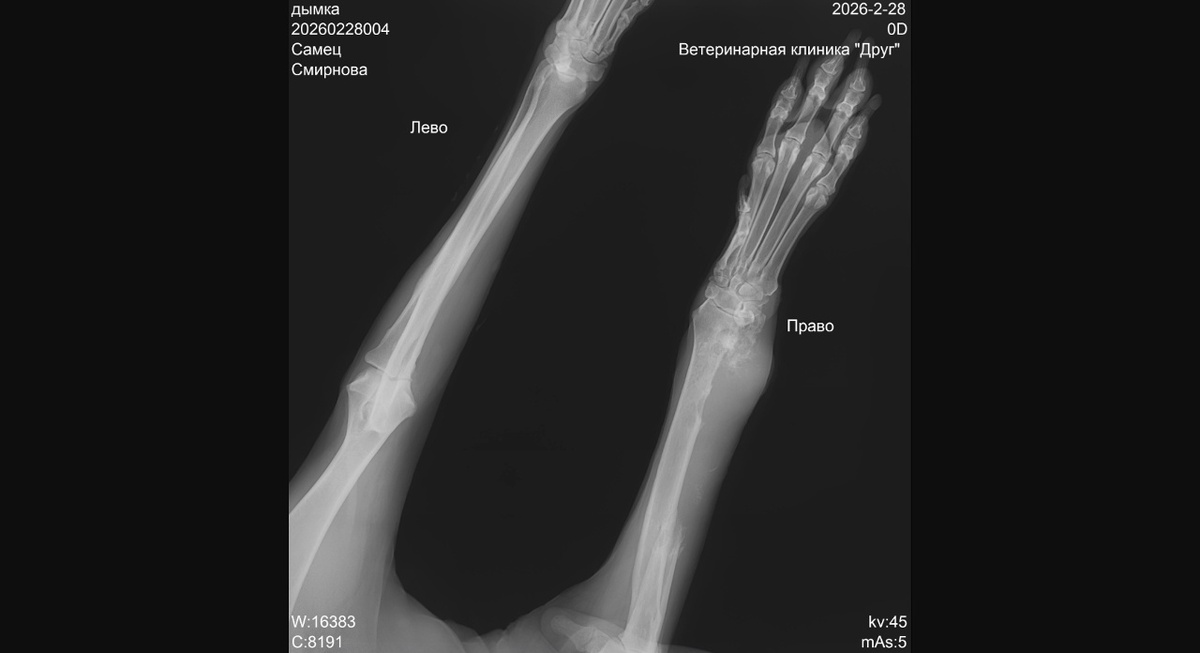

Получили Дымкин рентген и решили показать его вам.

Ну я не вижу растворившейся кости в суставе - опухший сустав вполне даже не плохо рассматривается. Честно говоря, думала что будет видно гораздо хуже из за опухлости. Но мы не врачи и в рентгене не понимаем, но предварительно все не хорошо

Рентген показали онкологу.